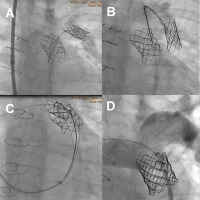

Figure 1

A – Melody valve embolized to the left pulmonary artery. B – Embolized Melody valve held with loop. C – Melody valve with two guidewires positioned in the left and right pulmonary artery held with the loop. D – Final result with competent implanted Melody valve

A Melody valve was advanced over a Cook Lunderquist wire (Cook Medical, USA) positioned in the left posterior basal artery. During deployment, an episode of ventricular tachycardia occurred, leading to valve dislodgement from the balloon to the proximal part of the delivery system. An attempt to reposition the valve on the delivery balloon was unsuccessful, and ultimately the valve embolized to the left pulmonary artery (Figure 1 A).

First, we exchanged the Ensemble delivery system for a long 14F Dryseal sheath (W. L. Gore, USA) and introduced a 20 × 45 mm BIB balloon over the guidewire. Using the partially inflated balloon and the long sheath, we repositioned the valve back into the landing zone. However, during inflation of the outer balloon, the valve slipped again and embolized back into the left pulmonary artery.

A second rescue strategy involved grasping the stent strut using a 20 mm Multi-snare (Pfm Medical, Germany) (Figure 1 B) and retrieving the valve into the pulmonary trunk. To prevent further displacement during deployment, two Amplatz Super Stiff guidewires (Cook Medical, USA) were inserted through the valve into the right and left pulmonary arteries – the “buddy wire” technique [2] (Figure 1 C). After releasing the valve from the snare, we advanced a 20 × 40 mm Atlas balloon over the guidewire into the lumen of the Melody valve and fully expanded the valve within the pulmonary trunk. Subsequently, we performed a redilation of the Melody valve with a 22 × 40 mm Atlas balloon. Final angiography confirmed optimal valve positioning with a residual systolic gradient of 7 mm Hg and no regurgitation (Figure 1 D).